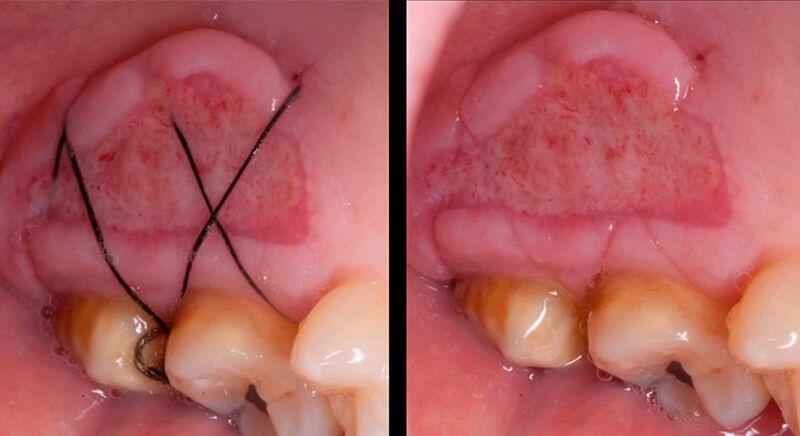

The socket was filled with a xenograft after the extraction and a graft of connective tissue was placed in the vestibular area of the two upper central incisors.

The tissue with epithelium was taken from the palate and de-epithelialized outside of the mouth. This obtains a lamina propria graft with better density and quality than if it were obtained with a single incision to the palate.